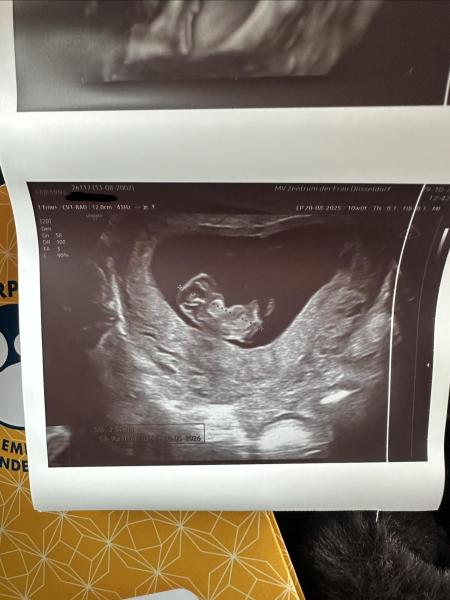

Hallo meine Lieben, ich müsste bei 10+0 sein. Gestern beim Termin habe ich diese schöne US Bilder bekommen. Die aktuelle SSL beträgt 2,84 cm, das kommt mir ein bisschen klein vor... Der Arzt sagt es sieht alles gut entwickelt aus, so wie es sein soll. Das kleine hat auch ordentlich gezappelt so war es schwierig alles auf das US Bild zu bekommen... Mir fehlen da bisschien die menschlichen Züge ... einbisschien kann man ja schon erkennen...  Sahen eure Ultraschallbilder ähnlich aus? Wie war eure SSL bei 10+0? Vielen dank eure Mamiibambii❤️